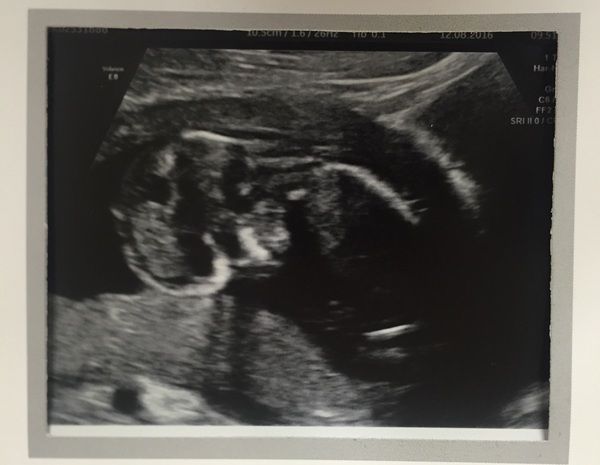

prettypinklady · 12/08/2016 21:24

Measured at 13+3, due 14th Feb.

Baby was been awkward and was upside down. (Turn upside down to see).Was wriggling like crazy. Grin